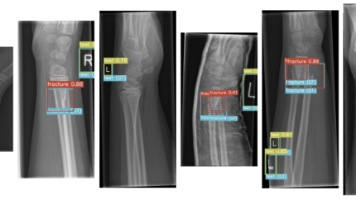

本文探讨了如何运用YOLOv7解决小儿腕骨X光检测难题。针对GRaZZPEDWRI-DX数据集的高分辨率16位灰度影像和微小骨折目标特性,提出了四步解决方案:1)数据预处理实现张量格式转换;2)采用E-ELAN计算块防止特征流失;3)引入主头引导的软标签分配应对标注噪声;4)通过重参数化技术实现急诊级实时推理。这些方法有效解决了医疗影像检测中的微小目标识别、标注模糊性和实时性要求等核心挑战,为医学